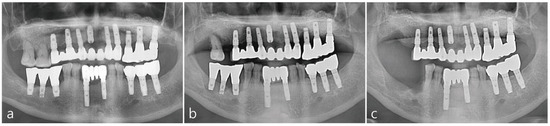

2.3. Postoperative Evaluation

In Figure 4a, complete radiographic bone fill was observed in the immediate post-operative panoramic radiograph. The implant was uncovered at 6 months post-operatively. After reflecting the buccal mucoperiosteal flap, the implant was surrounded by hard tissue up to the implant platform as illustrated in Figure 4b. The final prosthesis was delivered 2 months after the healing abutment was inserted. Two years after the delivery of the final prosthesis, a panoramic radiograph, Figure 4c, was taken to confirm the radiographic bone fill.

Figure 4. (a) Immediate post-operative panoramic radiograph. Intraoral bone augmented around the implant was observed. (b) Intra-oral photo taken 6 months post-operatively during the second stage procedure. (c) Panoramic radiographs taken two years after prosthesis delivery showed radiographic bone fill around the implant was maintained.